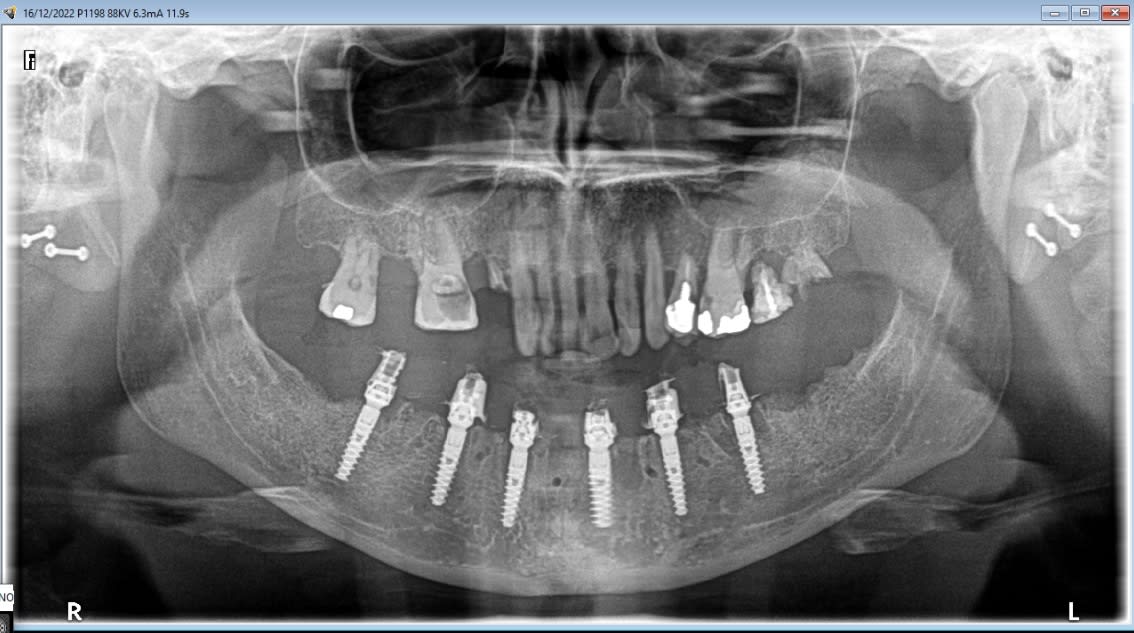

Et la pano

E7ekivq279p7yx0l1en7ld2td0xr - Eugenol